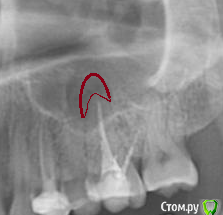

Дора Опубликовано 14 декабря, 2015 Поделиться Опубликовано 14 декабря, 2015 Добрый день! сегодня удалила зуб 26 из-за кистогранулемы. До этого стоматолог-терапевт предположил , что киста относится к 25 зубу. Хирург однозначно сказал, 26 и удалили. Когда удалил, я спросила про кисту , где она, но он даже не показал зуб. Сказал, что теперь организм все сам сделает! А я теперь думаю, может быть там не было кисты. скажите, дожно ли быть видно кисту, К какому зубу относится кистогранулема Прилагаю ОПТГ. спасибо Ссылка на комментарий

red_butler Опубликовано 14 декабря, 2015 Поделиться Опубликовано 14 декабря, 2015 На снимке периодонтит 2.6 зубаПочему не стали лечить? Ссылка на комментарий

Ker Опубликовано 14 декабря, 2015 Поделиться Опубликовано 14 декабря, 2015 (изменено) Два года мучаюсь полипозным риносиситом. Сделала 2 операции. А этот зуб был сначала лечен 7 лет назад. появилась боль при накусывании. Перепломбировали каналы 4 года назад. боль оставалась, врач развел руками. Потом начались лор - проблемы. После первой операции через 11 месяцев все вернулось - полипы и в пазухах образование грибкового муцина. Аллергия, предполагаемая врачем. на грибы - тесты 0. Сделала ОПТГ - нашли кистогранулемы, сказали срочно удалять. Мне важно сейчас знать, точно ли это 26 зуб и где киста, ее должны были удалить. От врача ничего не добилась.Кисты нет, есть периодонтит.Всё заживёт теперь уж.Да, 26 зуб. Изменено 14 декабря, 2015 пользователем Ker Ссылка на комментарий

red_butler Опубликовано 14 декабря, 2015 Поделиться Опубликовано 14 декабря, 2015 Спасибо. неужели такой важный зуб можно было сохранить? и лор, и стоматалог в один голос - кистогранулема, не лечить, а удалять.Если судить только по снимку, то да, зуб можно было сохранить. Ссылка на комментарий